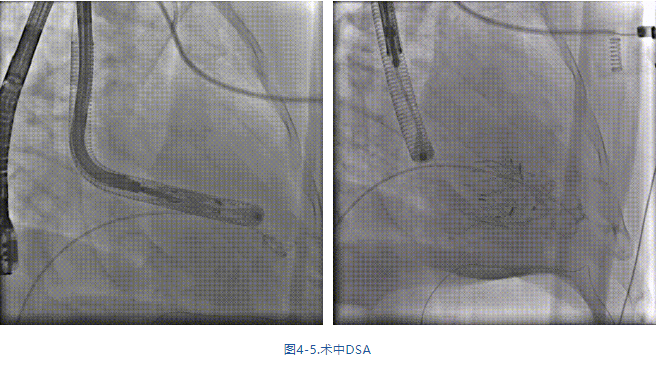

手術(shù)在全麻狀態(tài)下進(jìn)行,采用經(jīng)右側(cè)頸靜脈入路,在TEE和DSA的指引下緩慢送入輸送器進(jìn)入體內(nèi),進(jìn)入右室后釋放室間隔錨定裝置,旋轉(zhuǎn)輸送器,使得錨定裝置對準(zhǔn)室間隔面;釋放前瓣夾持件,確定夾持件位于右室側(cè)后釋放人工瓣膜盤片,DSA及超聲確認(rèn)盤片位于右房側(cè),并適時調(diào)整瓣膜的同軸性。在DSA和超聲的監(jiān)視下調(diào)整室間隔錨定件貼合室間隔,釋放室間隔錨定裝置。再次確認(rèn)瓣膜的穩(wěn)定性和同軸性后,將輸送器撤出體內(nèi),最終完成瓣膜植入(圖4-5),手術(shù)室即刻拔除氣管插管。術(shù)后超聲提示人工三尖瓣同軸性良好,瓣架固定牢靠,無反流和瓣周漏,術(shù)后三尖瓣平均跨瓣壓差顯著降低。